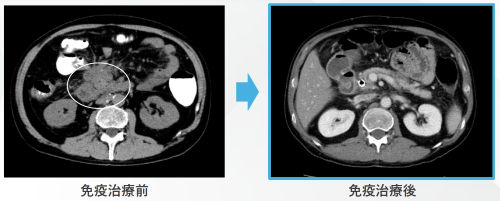

치료 시작 전 CT에서는 복막에 퍼져 있던 종양이 뚜렷하게 보였습니다.

하지만 불과 몇 달 후,

재촬영한 CT에서는 암 병변이 완전히 사라진 것이 확인되었습니다.

의료진의 말 그대로, “종양이 사라졌다(완전 관해 CR)”는 결과였습니다.